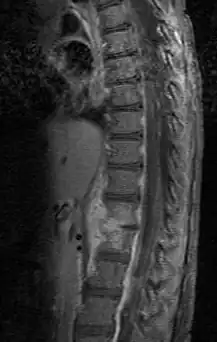

| Discitis in a 2 year old child. | |

Diagnosis is usually apparent on MRI, although plain X-rays and CT examinations can be suggestive. The MRI will reveal air changes in the disc and possibly even external involvement involving the bone or epidural regions. A biopsy may be performed and helps with diagnosis in some cases but often an organism is not obtained. C-reactive protein levels and ESR levels will be elevated and are useful for treatment. The white blood cell count may be normal.[5][6]